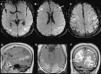

La afasia es una alteración adquirida del lenguaje debida a una lesión cerebral, que se caracteriza por errores en la producción, la denominación o la comprensión del lenguaje. Aunque la mayoría de las afasias suelen ser mixtas, desde un punto de vista práctico se clasifican en diferentes tipos según sus rasgos clínicos principales: afasia de Broca, afasia de Wernicke, afasia de conducción, afasia transcortical y alexia con o sin agrafia. Presentamos los hallazgos clínicos de los principales subtipos representándolos con casos radiológicos, y proporcionamos una revisión actualizada de la red del lenguaje con imágenes de resonancia funcional y de tractografía.

Aphasia is an acquired language disorder due to a cerebral lesion; it is characterized by errors in production, denomination, or comprehension of language. Although most aphasias are mixed, from a practical point of view they are classified into different types according to their main clinical features: Broca's aphasia, Wernicke's aphasia, conduction aphasia, transcortical aphasia, and alexia with or without agraphia. We present the clinical findings for the main subtypes of aphasia, illustrating them with imaging cases, and we provide an up-to-date review of the language network with images from functional magnetic resonance imaging and tractography.